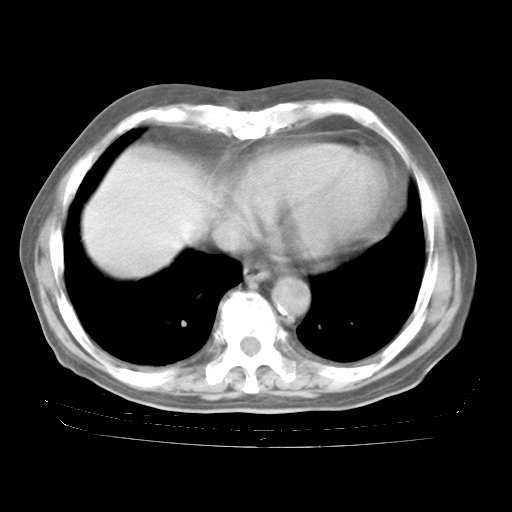

4月28日肺部CT——再次出现类似去年5月9日——透光度降低,“间质性”改变。